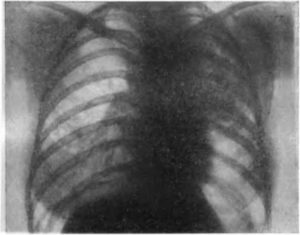

- Лучевая диагностика. Рентгенография и КТ грудной клетки являются наиболее информативными методами исследования диафрагмы. На рентгенограмме визуализируется высокое расположение одного из куполов (уровень II–V ребра). При рентгеноскопии обнаруживается парадоксальное движение диафрагмального свода. Использование контраста позволяет выявить перегибы пищевода, желудка, смещение органов пищеварения кверху. КТ наиболее точно определяет степень релаксации, помогает распознать вторичную патологию внутренних органов.

Основным методом диагностики релаксации диафрагмы, как и диафрагмальных грыж, является рентгенологическое обследование больного.

У некоторых больных с релаксацией диафрагмы клинически удается заподозрить наличие диафрагмальной грыжи, но провести дифференциальную диагностику между грыжей и релаксацией диафрагмы без применения рентгенологического исследования практически почти не представляется возможным. Лишь особенности характера развития и течения заболевания способны оказать некоторую помощь при решении этой задачи.

Единственным методом, позволяющим отличить релаксацию диафрагмы от грыжи, является рентгенологическое исследование. Оно дает возможность установить, расположены ли смещенные органы под или над диафрагмальной перегородкой.